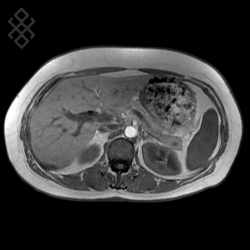

IRM Hépatique